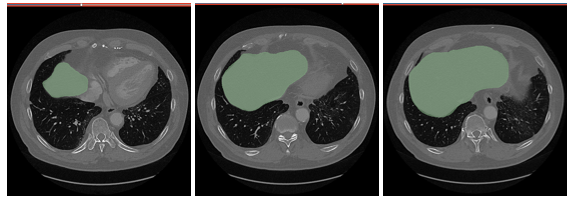

{Fig01. Labeled mask with raw image and without raw image}

{Fig.02 Labeled mask with raw images}

{Fig.02 MRI image with Liver region}

완성된 모델을 지속적으로 학습시킴에 따라 위와 같은 Test image 로 prediction 을 실시하였다. 위의 이미지는 Segmentation 을 목표가 존재하는 이미지이다. 결과는 이하와 같다.

완성된 모델에 이미지를 Axis 방향으로 연속적인 Prediction 을 진행한 결과이다. Fig.12 는 Predicted region 이 Green 으로 마킹되었다. 시각적으로는 다양한 크기의 target region에 prediction 이 잘 마무리 된 것으로 확인된다.

Fig.13 ~ Fig.15 는 연속적인 이미지를 다시 3D slicer 에서 출력한 결과이다. Fig.13 과 Fig.14 에서는 Ground Truth image와 Prediction이 매우 잘 맞는 것을 볼 수 있다.